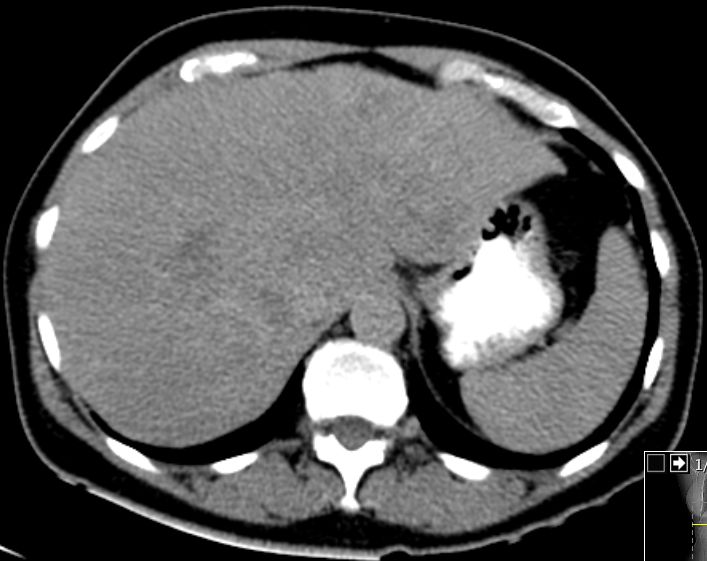

In der arteriellen Phase Unregelmäßigkeiten.![]() | ||